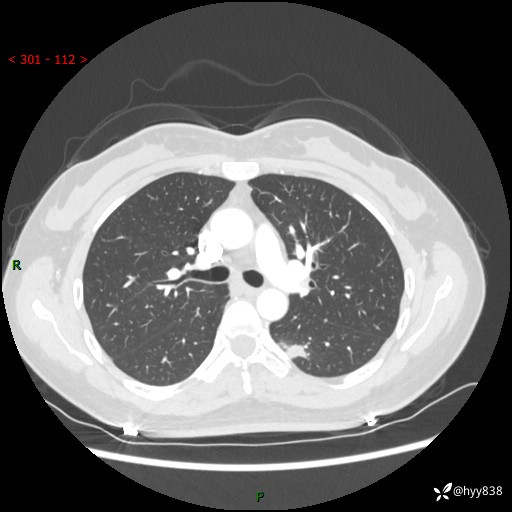

【患者信息】:36岁/女

【主诉】:左侧下胸部阵发性疼痛2周,乏力1周

【现病史及既往史】:患者自诉2周前饮酒后出现左侧下胸部阵发性疼痛,不随呼吸改变,无咳嗽咳痰、头晕头痛、咳血、呼吸困难等不适,于当地第一人民医院查胸部CT提示肺部感染,随后前往我院门诊给予抗感染(左氧氟沙星)治疗1周,自诉胸痛较前好转,感乏力、头晕,偶尔干咳,无咳痰,无发热、畏寒、胸闷、咯血、四肢酸痛、腹泻、腹痛等不适,门诊复查胸部CT提示:左肺下叶感染,病灶较前增加增大,遂以“肺部感染”收入我科。 起病以来,患者精神、饮食、睡眠可,大小便正常,体力体重无明显变化。

【检查】:胸部CT增强(外院平扫)